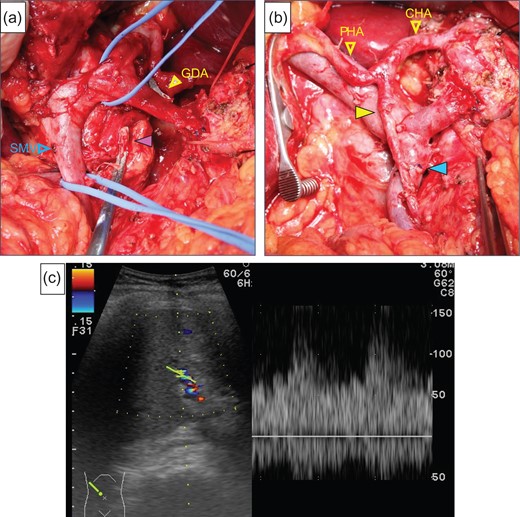

After laparotomy we identified the MAL, which had compressed the origin of the CA (Fig. 2a), and Doppler ultrasonography showed that the hepatic arterial flow was hepatopetal, but the common hepatic arterial flow was hepatofugal (no record available). First, the MAL was divided (Fig. 2b). After clamping the GDA (Fig. 2c), the hepatic arterial flow was not satisfactory (Fig. 2d). We continued the operation under GDA clamping. Finally, the specimen was connected only by the IPDA, SMV and GDA. The IPDA and aneurysm were ligated and divided (Fig. 3a). At this time, 92 min after clamping the GDA, however, the hepatic arterial flow was not improved. We were able to preserve the GDA 10 mm from its root, we divided the GDA and SMV and extracted the specimen. Arterial reconstruction by end-to-end anastomosis of the GDA and MCA was performed by plastic surgeons (Fig. 3b). After reconstruction, the hepatic arterial signal was improved (Fig. 3c).

(a) The median arcuate ligament (green arrow) compressed the CA. (b) Compression of the origin of the CA by the ligament was released. (c) The image shows that the GDA was clamped. (d) We checked the hepatic artery flow under GDA clamping, but the flow had not improved satisfactory.